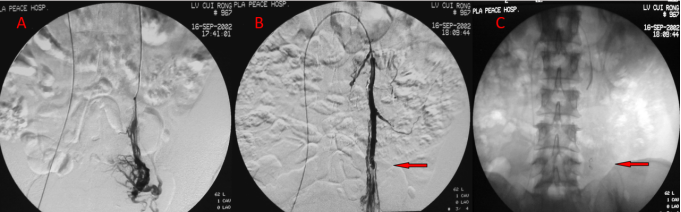

病例1:

图:A:左侧卵巢静脉造影B,C:左侧卵巢静脉栓塞造影(箭头示弹簧圈)

★ 栓塞技术要点

栓塞指征:

卵巢静脉直径 ≥ 10mm

中重度卵巢子宫静脉丛曲张

曲张静脉跨越中线

栓塞材料:首选弹簧圈,直径应大于靶静脉1-2mm。

栓塞策略:提倡 “三段式栓塞法” ——对卵巢静脉的远段(盆腔内)、中段、近段(汇入肾静脉或下腔静脉处)进行彻底栓塞,以防侧支复发。